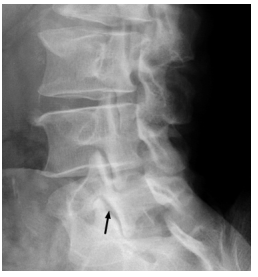

Um paciente atleta de alto rendimento queixa-se de dor crônica em coluna lombar, há cinco meses, relacionada com as respectivas atividades esportivas. Nega sintomas de retenção ou incontinência urinária/fecal, febre, sintomas urinários ou irradiação da dor para membros inferiores.

Considerando-se esse caso clínico e a radiografia apresentada, qual esporte apresenta maior probabilidade de ser o praticado pelo paciente?